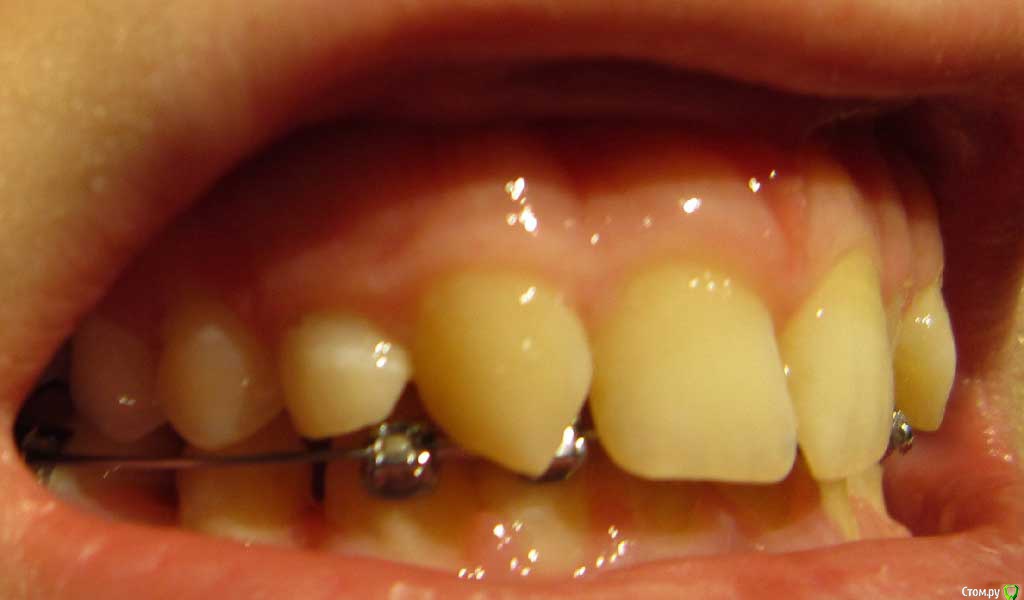

Сейчас мне 17 лет. На лечении у ортодонта с августа 2013 года. Удалили молочные пятерки и стали сдвигать шестерки к передним зубам. На верхнюю челюсть она ставить брекеты не стала. Осенью 14 года врач ушла в декрет.

Пришел новый врач который предложил все сделать несколько иначе: поставить брекеты на обе челюсти, все выравнять и освободить место под будущие импланты: вместо пятерок снизу и второго слева резца сверху -, а пока на их место поставить коронки. Также врач назвал сроки: около 1 года.

Сверху слева отсутствует зачаток второго резца, вместо него находится клык и молочный зуб левее. Внизу нет зачатков пятерок.